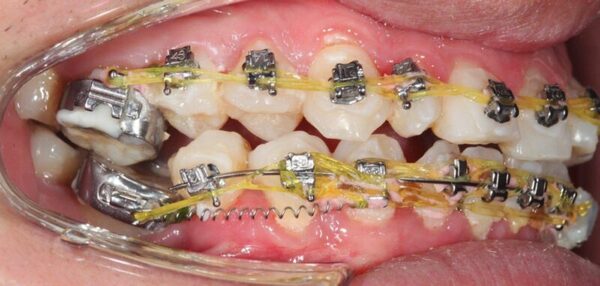

Dấu hiệu đầu tiên cho thấy ca niềng răng của bạn không thành công đó chính là chân răng lệch, bị tiêu chân răng hoặc thậm chí là gãy răng. Niềng răng tức là tác động lực để căn chỉnh, dịch chuyển răng về vị trí mong muốn trên cung hàm. Tuy nhiên, nếu như thực hiện sai kỹ thuật, tác động lực quá mạnh khiến răng dịch chuyển quá nhanh sẽ khiến cho chân răng của bạn bị tiêu hoặc thậm chí là gãy răng.

Cũng giống như dấu hiệu cho thấy niềng răng thất bại thì nếu như trong quá trình niềng răng mà chân răng của bạn bị tiêu, lệch hoặc bị gãy mà không có phương pháp giải quyết kịp thời, hiệu quả thì cũng có thể khiến cho kết quả niềng răng của bạn thất bại.